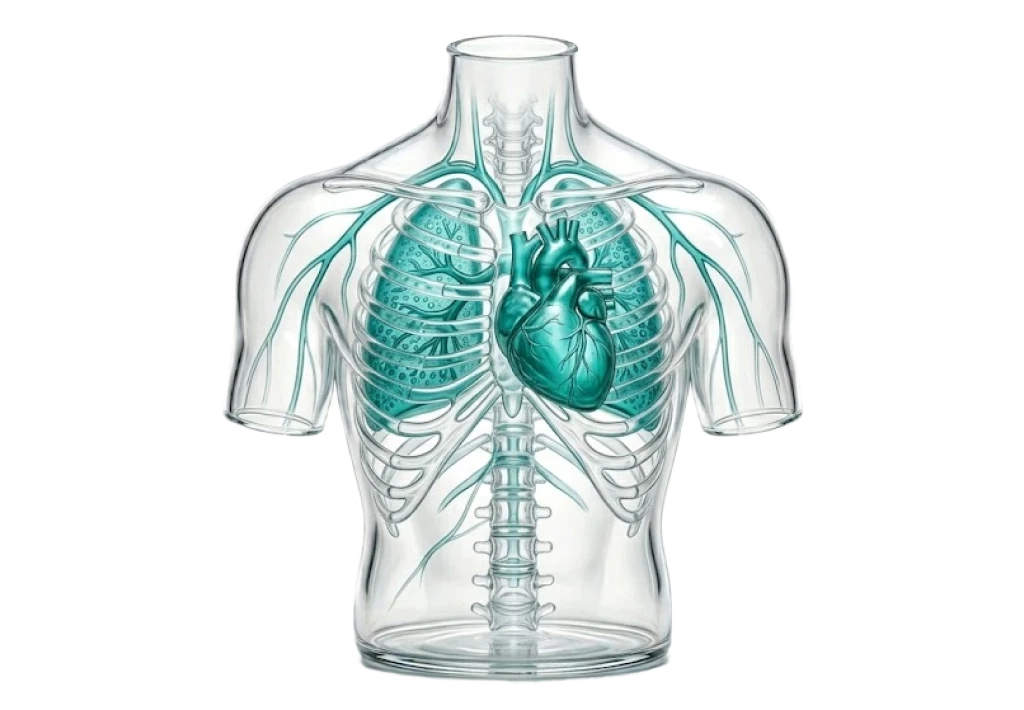

Кардиология

Пульмонология

Alash Expert Clinic is a multidisciplinary medical center in Almaty

Premium medical center "Alash"